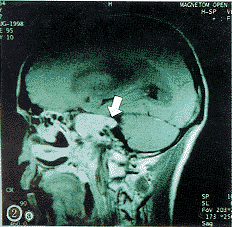

(1)小脑脑桥角肿物:指在岩锥或岩枕缝的后方或上方,见弧形隆起的软组织肿物。该肿物在平扫的CT上呈中等密度,与其周围脑结构的密度对比差,故易漏诊;在增强的CT上呈高密度;在平扫的MRI上呈中、高信号,增强后信号更高,显示更清晰,见图1,2。

a轴位 b冠状位 c矢状位

图1 增强的T1加权MRI示复发性鼻咽癌累及右侧小脑脑桥角(黑、白箭头)

肿物在小脑脑桥角的近内侧者28例(图1),在近内耳门者2例。肿物最大直径为1.0~6.5?cm。在原始的影像学报告书上诊断小脑脑桥角占位的仅6例。2例小脑脑桥角肿物在增强和不增强的MRI上均显示其是由海绵窦沿三叉神经向后蔓延达桥池的(图2a),其中1例尚显示其海绵窦的肿物是同侧的NPC咽旁复发经由扩大的卵园孔沿下颌神经向上蔓延而来的(图2b),此种沿神经扩展的现象在CT上即使增强也不能显示。6例于放射治疗后复查MRI或增强CT,其中5例CPAI消退(图2c),1例缩小。

(2)占位效应:指CPAI较大,挤压毗邻的脑干,使之向健侧移位(图1a),环池两侧不等宽。本组10例阳性(33.3%)。